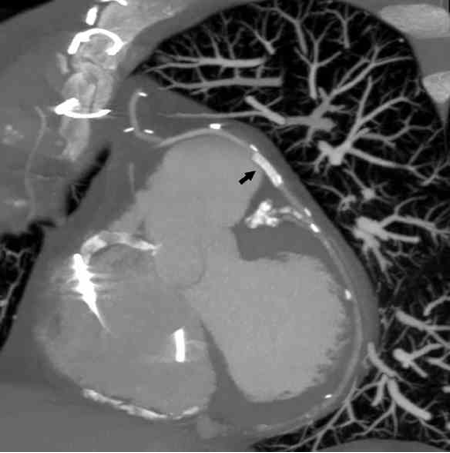

Figure 1. Contrast extravasation with jet stream effect was noted at the dilated site of the saphenous vein graft (SVG; arrowhead) (click thumbnail to view larger image).

A 66-year-old man was admitted to our hospital with acute onset of chest tightness for 2 hours. He had a history of hypertension and end-stage renal disease (ESRD) and had undergone hemodialysis. He also had a 3-vessel coronary artery disease and had undergone coronary artery bypass grafting 1 year prior, receiving a sequential SVG to the right coronary artery (RCA), and obtuse marginal (OM) and left internal mammary artery (LIMA) to the left anterior descending artery (LAD). On physical examination, the patient was found to have a blood pressure of 157/98 mm Hg, heart rate of 84/min, and respiratory rate of 20/min. The cardiovascular examination results were unremarkable. A 12-lead electrocardiogram showed ST elevation in leads II, III, and aVF. Laboratory data showed normocytic anemia and poor renal function, which was related to the ESRD. From the ST elevation, we identified the artery causing the inferior wall acute MI and performed emergent coronary angiography within 90 minutes after the admission. The coronary angiography revealed 61% stenosis at the left main artery, 86% stenosis at LAD, and 77% stenosis at the ostium of the RCA. The bypass graft of LIMA to LAD was patent; however, an 87% stenosis at the proximal SVG to OM2 and RCA was noted. A percutaneous transluminal coronary angioplasty for the SVG lesion was performed immediately, using a 6 Fr JR 4 guiding catheter and EXTRA S’PORT wire (Abbott Vascular Devices). The initial activated clotting time (ACT) was 187 s, and the patient was heparinized with a bolus of 10,000 units before the procedure. First, a Sprinter 2.0 × 20 mm balloon (Medtronic) and then a Firestar 3.0 × 30 mm balloon (Johnson & Johnson) were used to dilate the lesion. Because of unsatisfactory results in comparison with the distal SVG size, a Maverick 4.0 × 30 mm balloon (Boston Scientific) was used next. After a single inflation at 10 atm, contrast extravasation with jet stream effect was noted at the site of the dilation (Figure 1).